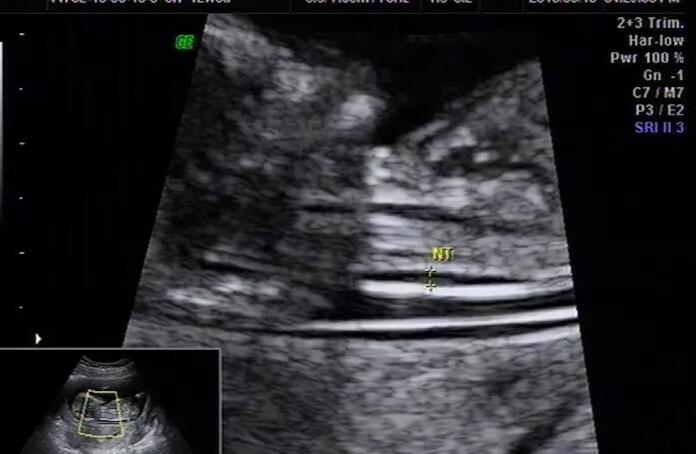

泰国试管成功率权威海参崴试管8万 2023年威海试管婴儿医院排名 ‘32周胎儿b超图片如何看男女’